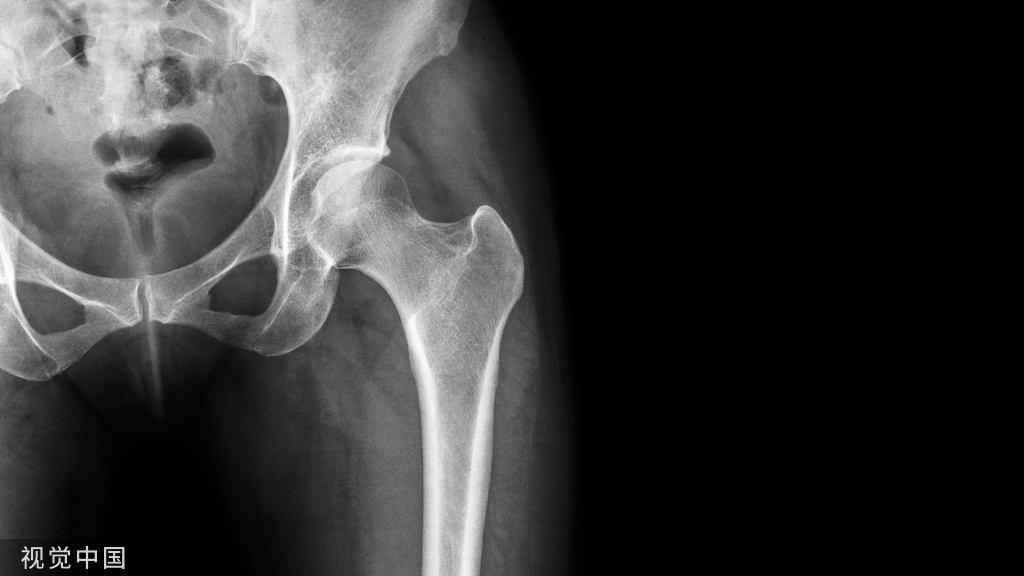

推荐意见1:DLSS是指由于退行性病变引起椎管、侧隐窝、神经根管等狭窄而引起的相应症状,不包括由于腰椎间盘突出、腰椎不稳、腰椎滑脱或脊柱侧凸引起的狭窄。

推荐意见2:DLSS的诊断依据:①有腰部、臀部及下肢痛,或伴有腰部僵直及马尾神经症状,有典型的间歇性跛行症状;②影像学检查可见椎管狭窄、神经根管狭窄、侧隐窝狭窄等改变;③临床症状、体征与椎管狭窄节段一致。